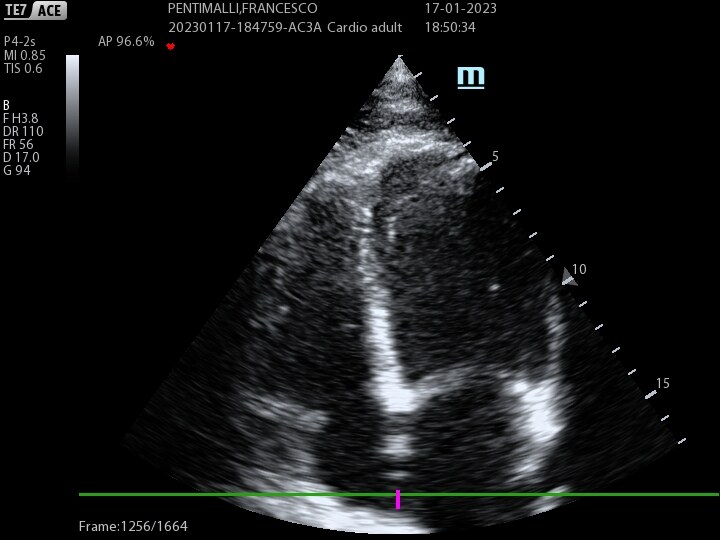

Ecocardiogramma color-doppler

L'ecocardiogramma color doppler transtoracico è un esame ecografico non invasivo e sicuro...